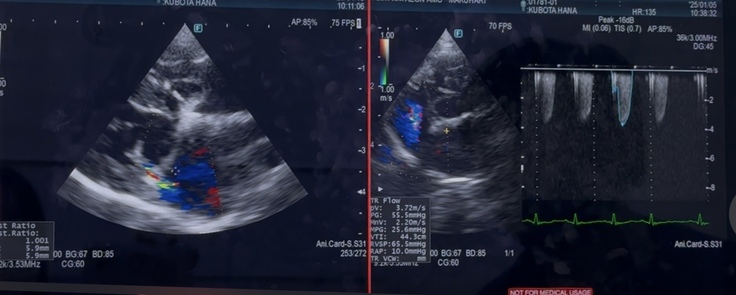

エコー上は、逆流は相変わらず残っていますが…

少量であり、悪化はみられませんでした

左心の大きさも、変わらず…

小さくはなっていませんでした

右心の三尖弁の逆流と肺高血圧症も、変わらず…中等度でした…